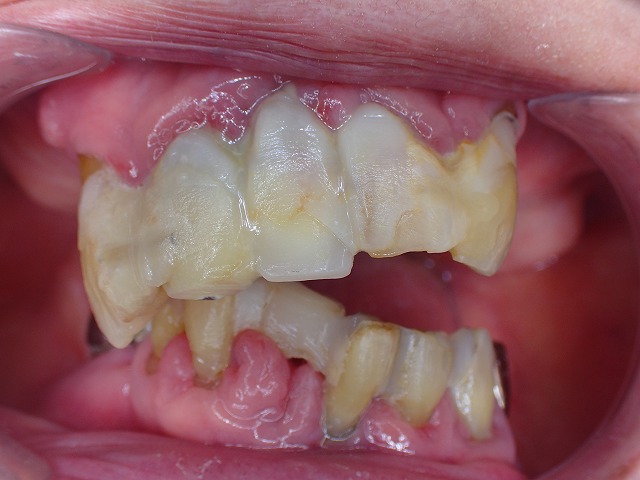

歯周病固定 実例3 歯を抜きたくないと15年以上 長期の観察管理・予防処置

末期中の末期 この状態でも15年以上維持できている

大切なのはご本人の自由意志

最後まで持たせたいという患者さんのご希望

コンポジットレジン充填の際に

それを連結することで、固定。

もっとも重要なことは歯肉の炎症に対する

歯周病処置 予防処置です。

咬み合わせのバランスにより、歯が移動しているので

左右が非対称です。

半分開口した状態です。